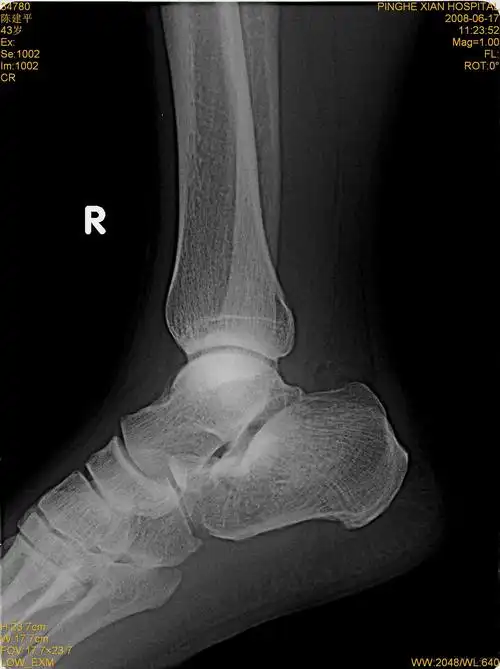

右足跟骨骨折